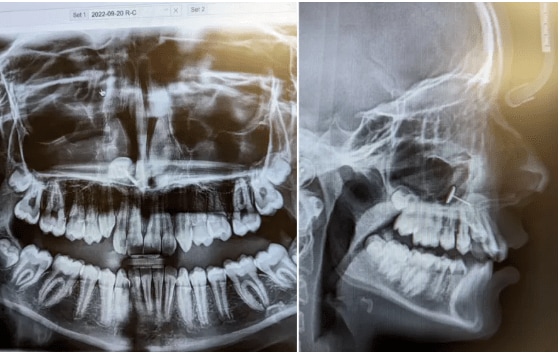

<歯科矯正のために歯医者を訪れた親子が目にしたのは、驚きのレントゲン写真だった>

「矯正歯科医が部屋に戻ってきて、X線画像をスクリーンに映したの。私たちは同時にそれを見て、しばらく何を見ているのか理解できなかった」と母親は本誌に語っている。

■副鼻腔に引っかかっている「まさかの物体」の正体は?...本文記事で詳しく読む

「矯正歯科医が部屋に戻ってきて、X線画像をスクリーンに映したの。私たちは同時にそれを見て、しばらく何を見ているのか理解できなかった」と母親は本誌に語っている。

■副鼻腔に引っかかっている「まさかの物体」の正体は?...本文記事で詳しく読む